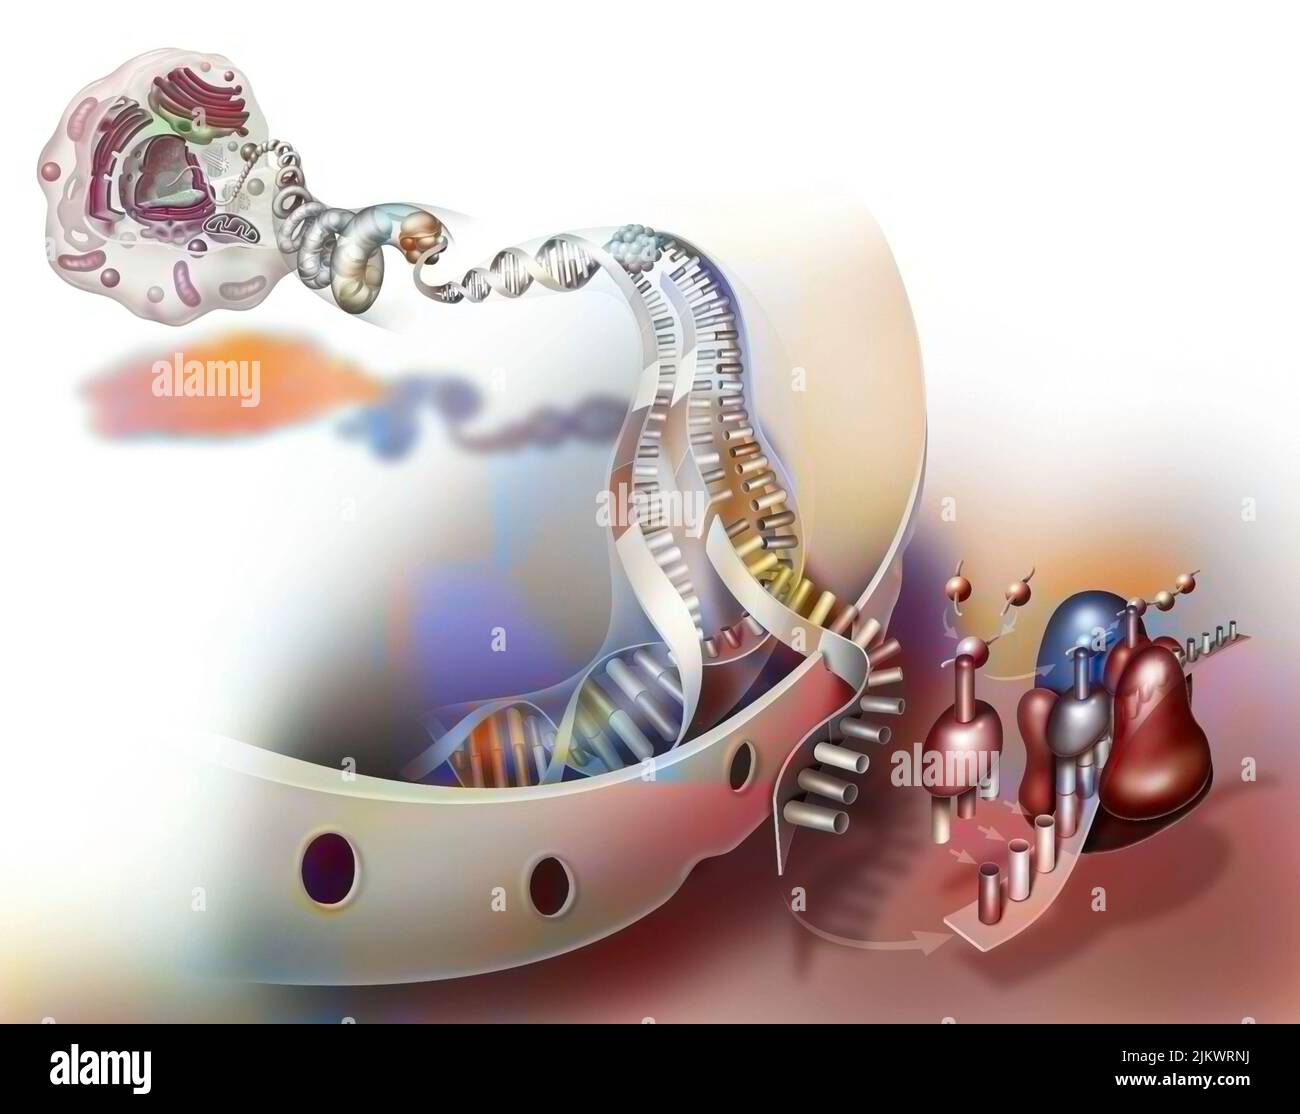

RF2JKWRMG–Thérapie génique : introduction de rétrovirus pour modifier les cellules de la moelle épinière mutées d'un nouveau-né.